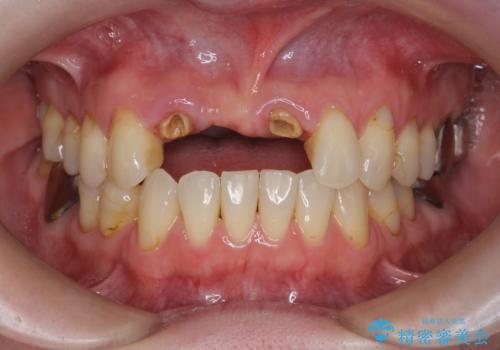

前歯が折れた 前歯部審美セラミックブリッジ治療

- ブリッジの根元が折れ、審美性の改善・治療を求めて来院されました。

保存の難しい歯を抜去しロングブリッジによる補綴を選択しました。

かみ合わせの観点からインプラント治療は難しく、入れ歯も希望されなかったためブリッジによる補綴を選択しました。